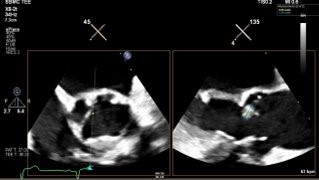

A 55-year-old male with well-controlled HIV presented with acute febrile illness, executive dysfunction, and visuo-cerebellar deficits. Initial concerns included meningoencephalitis, CNS lymphoma, and progressive multifocal leukoencephalopathy. Extensive infectious workup was unrevealing. Brain MRI revealed numerous bilateral hyperintense lesions. CT chest/abdomen identified bilateral axillary adenopathy, right pulmonary embolus, and splenic infarcts. Arterial Doppler showed a right tibial artery occlusion. Transthoracic echocardiography demonstrated aortic valve vegetations. Despite multiple embolic events, all blood cultures remained sterile, raising concern for blood culture–negative endocarditis, malignancy-associated endocarditis, and autoimmune etiologies. This prompted further serological testing for C. burnetti, B. henselae, Brucella and tumor markers, all of which were unremarkable.

Autoimmune evaluation revealed ANA >1:1280, anti-dsDNA positivity, and low complement levels, meeting the 2019 American College of Rheumatology criteria for SLE (12 points). Transesophageal echocardiography confirmed multiple echogenic densities on the aortic valve, consistent with a diagnosis of LSE in the setting of newly diagnosed SLE. LVEF was moderately reduced (35–40%) with global hypokinesis. The patient was started on therapeutic anticoagulation and guideline-directed therapy for heart failure, with rheumatology consulted for long-term treatment.